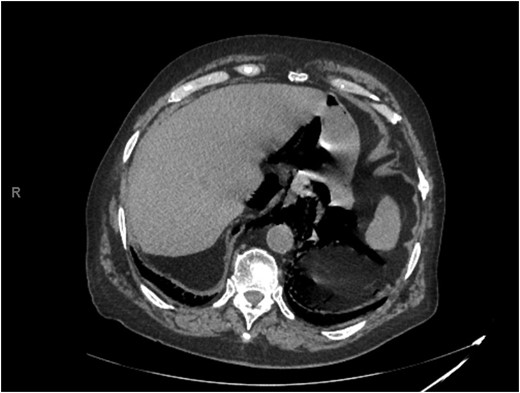

The patient subsequently became tachycardic and tachypneic. Increased work of breathing was noted with an oxygen saturation of 63%. The patient was placed on a non-rebreather mask, and his oxygen saturation subsequently increased to 99%. Shortly after the non-rebreather was placed, the patient became somnolent, responsive only to sternal rub. The patient was intubated for airway protection and plans made for transport to the SICU. Portable semi-upright chest x-ray demonstrated an endotracheal tube in proper position, no pneumothorax, and possible left pleural effusion. The tip of the NGT was not initially visualized (Fig. 3).

Portable semi-upright chest x-ray demonstrating an endotracheal tube in proper position, no pneumothorax, and possible left pleural effusion. No evidence of widened mediastinum or free air under the diaphragm. The nasogastric tube is visible coursing through the right internal jugular vein to the superior vena cava. The tip of the nasogastric tube is not visible.